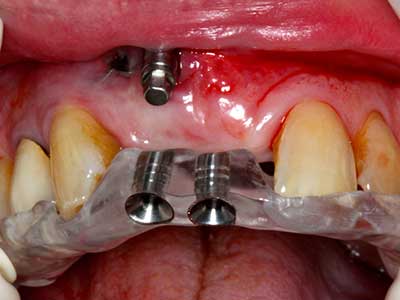

Si es preciso realizar intervenciones quirúrgicas en las que el hueso está en contacto directo con estructuras sensibles, como son los vasos sanguíneos o los nervios, los instrumentos rotativos presentan un enorme potencial de provocar lesiones iatrogénicas. Así, precisamente en la representación de nervios después de una lesión iatrogénica, o en el transcurso de la lateralización de un nervio para resecciones, reconstrucciones o incorporación de implantes, los equipos piezoeléctricos pueden resultar muy útiles para preparar la tapa ósea y retirar las partes de tejido duro cercanas al nervio (fig. 17-20). Por lo general, un ligero contacto del cordón nervioso con el inserto piezoeléctrico no tiene consecuencia alguna; ahora bien, un procedimiento poco cuidadoso con movimientos tipo sierra o piezas de trabajo sobre la base ósea aún existente puede provocar lesiones nerviosas temporales o incluso permanentes. Con todo, el riesgo de sufrir una lesión de este tipo se considera significativamente inferior que en los casos en los que se utilizan sierras y fresas (Pereira, Gealh et al. 2014).